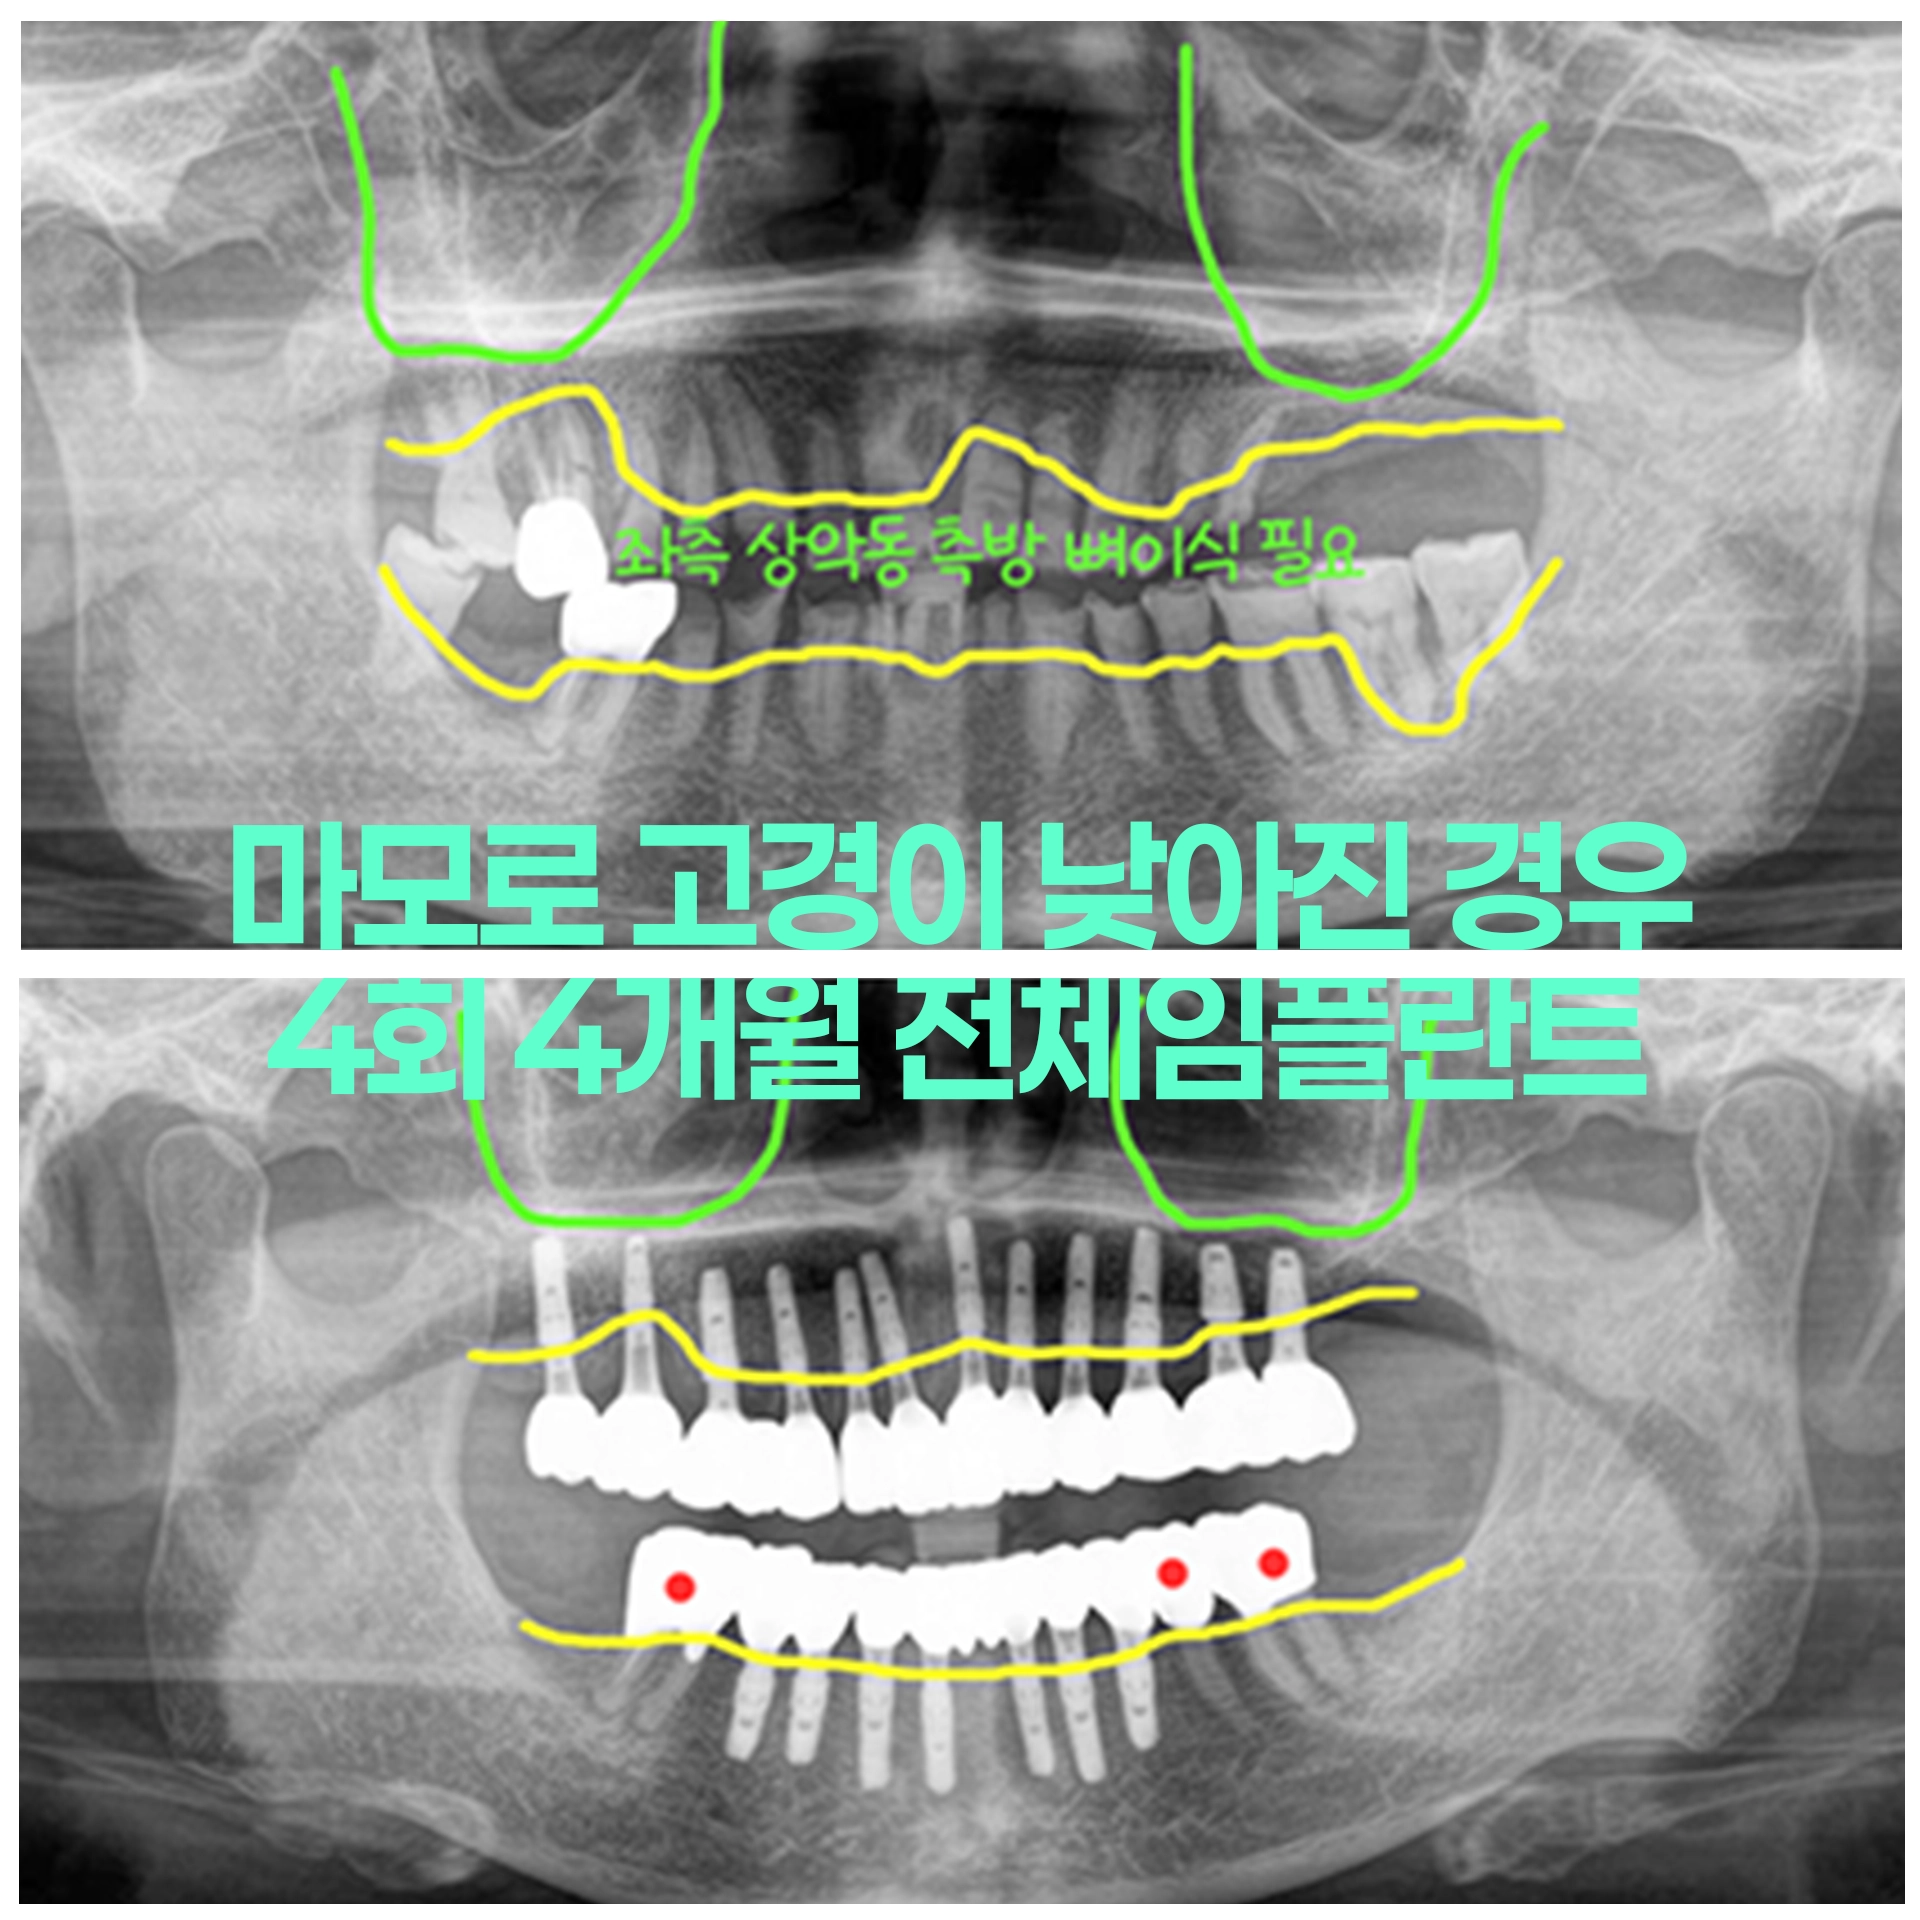

부분틀니 장기간 사용 고경소실 교합이상으로 즉시하중 수술당일 임시치아 전체임플란트